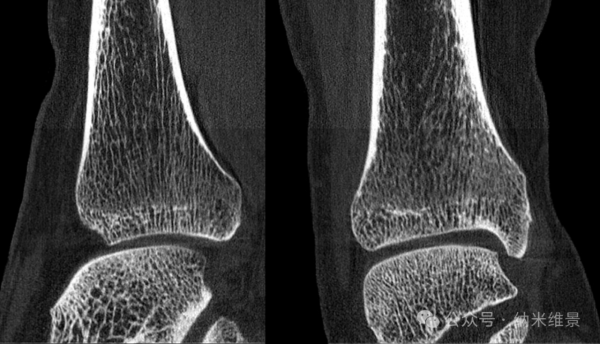

骨健康精准评估:从骨密度到微结构,预见骨折风险

当前临床金标准双能X线吸收测定法仅能提供二维骨密度,无法反映决定骨强度的关键——骨小梁三维微结构。

纳米维景相控阵CT的超高分辨率,使其能够对椎体骨小梁的微观参数进行精确量化,如骨体积分数(BV/TV)、骨小梁厚度(Tb.Th)、分离度(Tb.Sp)等。离体研究显示,其测量结果与相控阵CT显示结果高度一致。

在体研究进一步证实,这些微结构参数随年龄增长呈现显著恶化趋势,且诊断骨质疏松的效能优异,其中体积骨密度(vBMD)的AUC值高达0.986。这意味着相控阵CT能更早、更准确地识别骨折高风险人群,实现个性化预防。